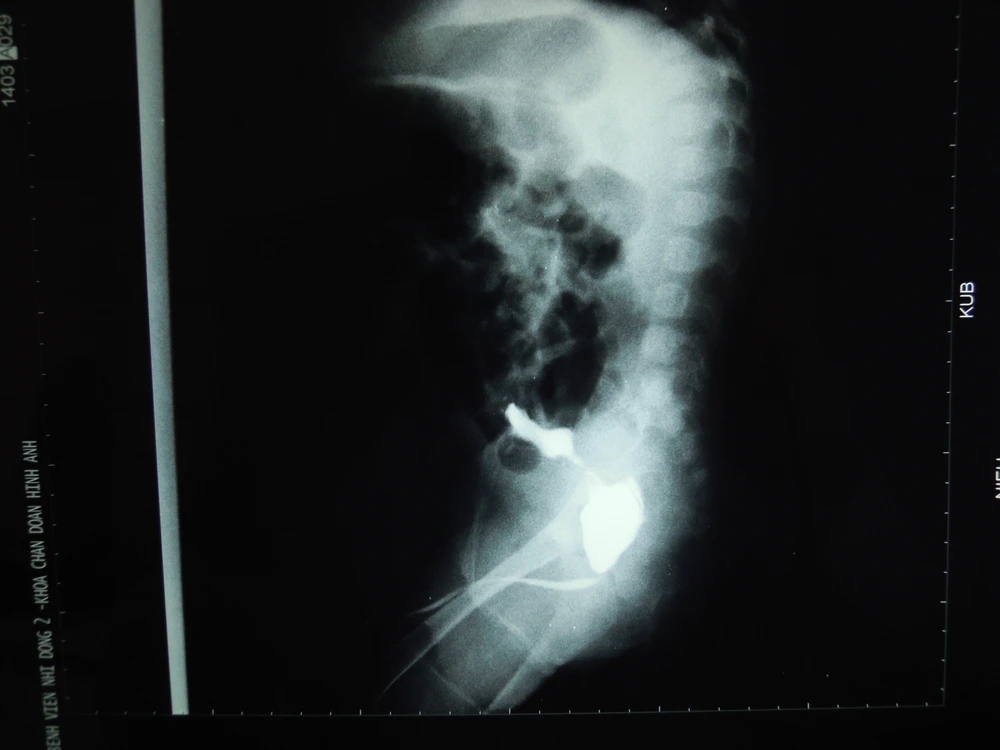

Bé nhập viện trong tình trạng bứt rứt, suy thận cấp. Kết quả thăm khám lâm sàng và hình ảnh chụp phim x-quang cho thấy bàng quang đã bị vỡ, bờ nham nhở. Siêu âm phát hiện ra hai niệu quản giãn, thận ứ nước 2 bên và nước tiểu tràn ngập trong ổ bụng. Hình ảnh niệu đạo cản quang cho thấy van niệu đạo sau là nguyên nhân chính.

Hình ảnh Cận lâm sàng thành bàng quang nham nhở